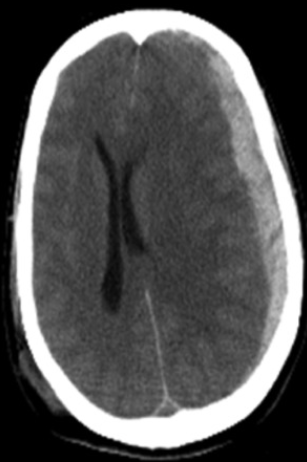

What is hydrocephalus, and what does it look like on CT head?

Hydrocephalus: Abnormal accumulation of CSF in brain ventricles and spinal cord

CT finding: Ventricles look swollen with loss of sharp points, with dark colour (hypodense due to fluid accumulation)